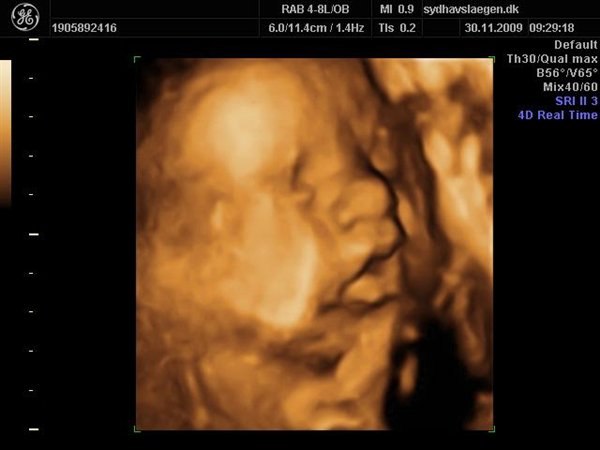

Nej det er godt nok noget så facinerende at man kan se babyerne inden i maven udefra, jeg forstår det godt nok ikke rigtig.

Men er bare glad for det kan lade sig gøre. Shit jeg kan næsten ikke vente til Onsdag. Har tænkt mig at købe to ens sutter i farven der nu passer på kønnet efter vi har fået det afvide også give dem til den kommende mormor og et sæt til den kommende farmor.

Hvor er det bare skægt, og syntes det er endnu mere skægt sådan som vi lige følger hinanden, mener jeg læste du havde været til første lægebesøg en eller 2 dage efter mig, og det samme var ved min første nakkefoldsscanning, der var du også et par dage efter, eller dagen efter, og nu tager du så 3d onsdag, hvor vi bare skal have kønsscanning på tirsdag